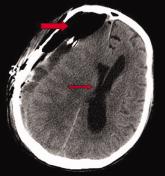

ArticleTension Pneumocephalus as Complication of Hematoma EvacuationAuthor:Andrew Cummins, MS, MDPublish date: June 5, 2009Read More